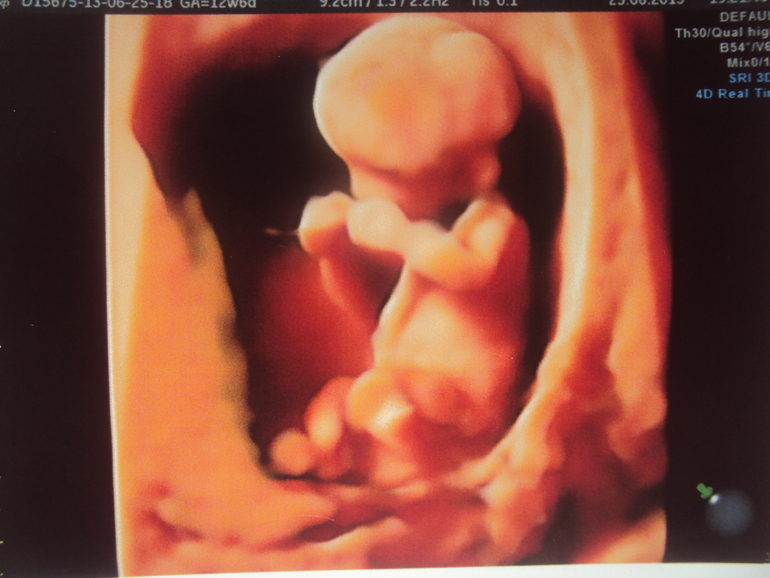

Сегодня такая довольная! пришла на скрининг в жк, посмотрели моих «Чука и Гека»❤️Растут маленькие! Не по дням, а по часам)

предыдущий скрининг делала на 29 неделе в «мать и дитя» для контроля развития, детки были 1250/1270, хорошенькие такие, пропорциональные, одним словом мамина и папина радость!

Единственное расположились очень уж забавно, нижний на попке сидит, а верхний поперёк живота лежит, голова слева, а попочку свою под правое ребро все пытается маме спрятать) и головами друг к другу - «две головы лучше», как говорится)) шушукаются там наверное днями и ночами.

Меня узистка спрашивает, как я вообще себя чувствую, какие жалобы, а я ей: ничего все ок, в среднем через день 7.000 шагов гуляю, веду активный образ жизни, и вообще кажется это самый «золотой» период какой-то получается: умудрилась даже на концерте на открытом воздухе побывать в субботу, октобрфест застать, дни рождения, заботы, хлопоты, лепка пельменей в запас), единственное говорю ей, что кажется немного животик потяжелел вчера и смеюсь, но в целом все хорошо, иногда схватывает и отпускает, как у всех, ничего особо не беспокоит, даже спина не болит после прогулок тьфу-тьфу, не то, что на 18-20 неделе, когда бывало ножку правую клинило из-за процесса растяжения связок. Бандаж сейчас даже не надеваю-нижнему детёнку не нравится💁♀️ Она на меня смотрит: говорит «ну вы молодец! Детишки уже 2014 и 1980!!! я аж опешила, стою в шоке на неё смотрю и до меня реально доходит что там уже 4 килограмма счастья! Срок опережаем на недельку (33 ставят по росту мужичков), так что на завтра выдали направление в род дом на консультацию-определяться с периодом родоразрешения

Единственный ньюанс это то, что детишкам до сих пор так удобно буквой «Г» лежать), так что скоро мой живот примет форму квадрата мне кажется😂 ну и как вытекающее отсюда последствие-КС (но говорят чудеса случаются и двойня переворачивается на таком сроке) ,а вот узистка говорит, пусть хоть верхний куда-нибудь повернётся, и то уже отлично будет) а то это совсем редкость, когда поперёк лежит детёнок: и маме не очень удобно, и матка сильнее растягивается. Шейка кстати хорошая опять же тьфу-тьфу🙏36, всю беременность так: 36-40